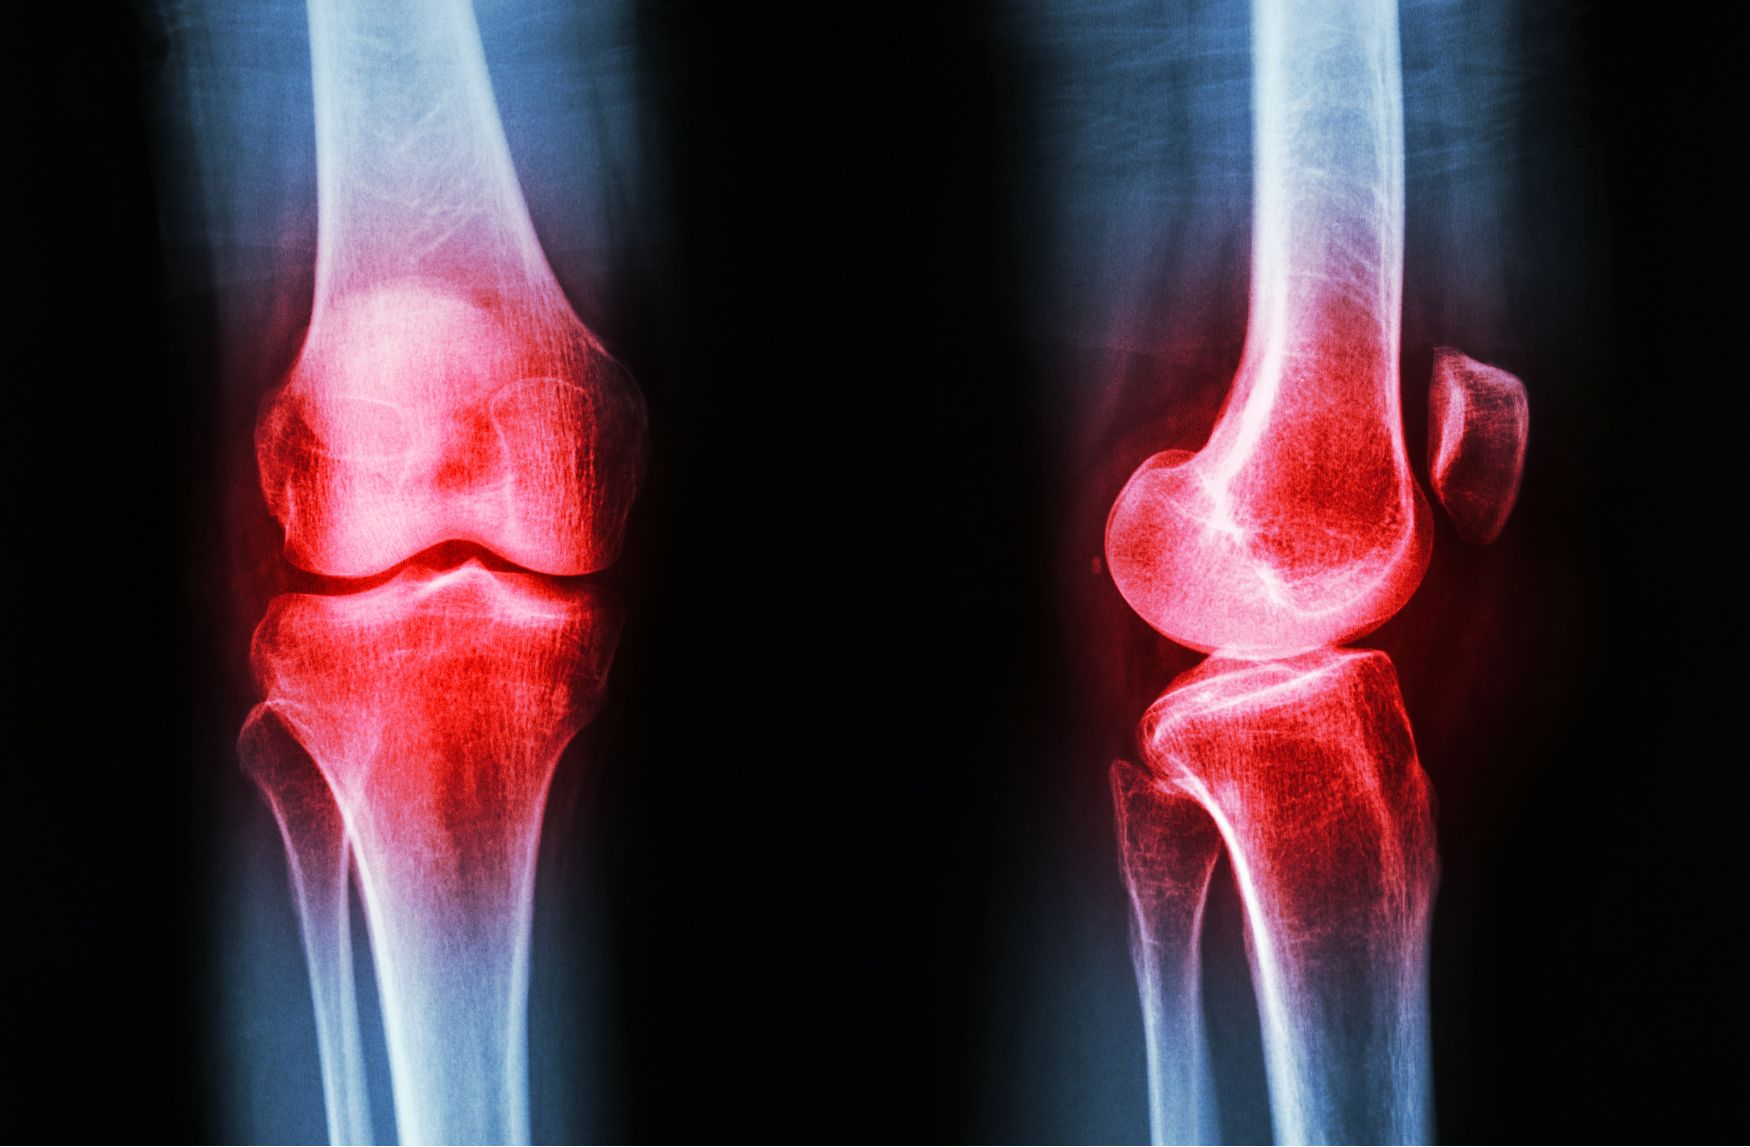

무릎 염증 증상 치료법 총정리

안녕하세요 문무남의 헬스케어입니다. 오늘은 무릎 염증에 관련한 내용을 알려드리려 하는데요, 원체 무릎이 안 좋으셨던 분들이나 무리한 신체 활동으로 인해 갑작스레 무릎이 붓고 열감이 나타나는 분들이 종종 계시곤 합니다. 이번 글에서 무릎 염증 증상과 치료법에 대해 자세히 알아보도록 하겠습니다.

기본적으로 무릎 관절은 뼈와 뼈와 만나는 부위로서, 지면으로부터 오는 충격과 하중을 완화해주는 완충 작용을 하는 역할을 합니다. 그러나 종종 여러 가지 원인에 의해 무릎 관절에 염증이 나타나곤 하지요.

여러분들이 무릎에 염증이 발생하는 원인은 주로 무릎에 가해지는 반복적인 충격, 부상, 비만, 노화 등이 있습니다. 이러한 이유들로 인해 무릎 연골이 손상되고 관절 주변의 조직에서 염증 반응이 나타나게 되는 것이죠.

일반적으로 무릎에 염증이 발생하면 주로 욱신거리는 통증, 붓기, 뻣뻣함, 열감 등의 증상들이 나타나게 되는데요. 제때 치료를 하지 않고 방치할 경우 관절 기능의 상실로 이어지기도 합니다